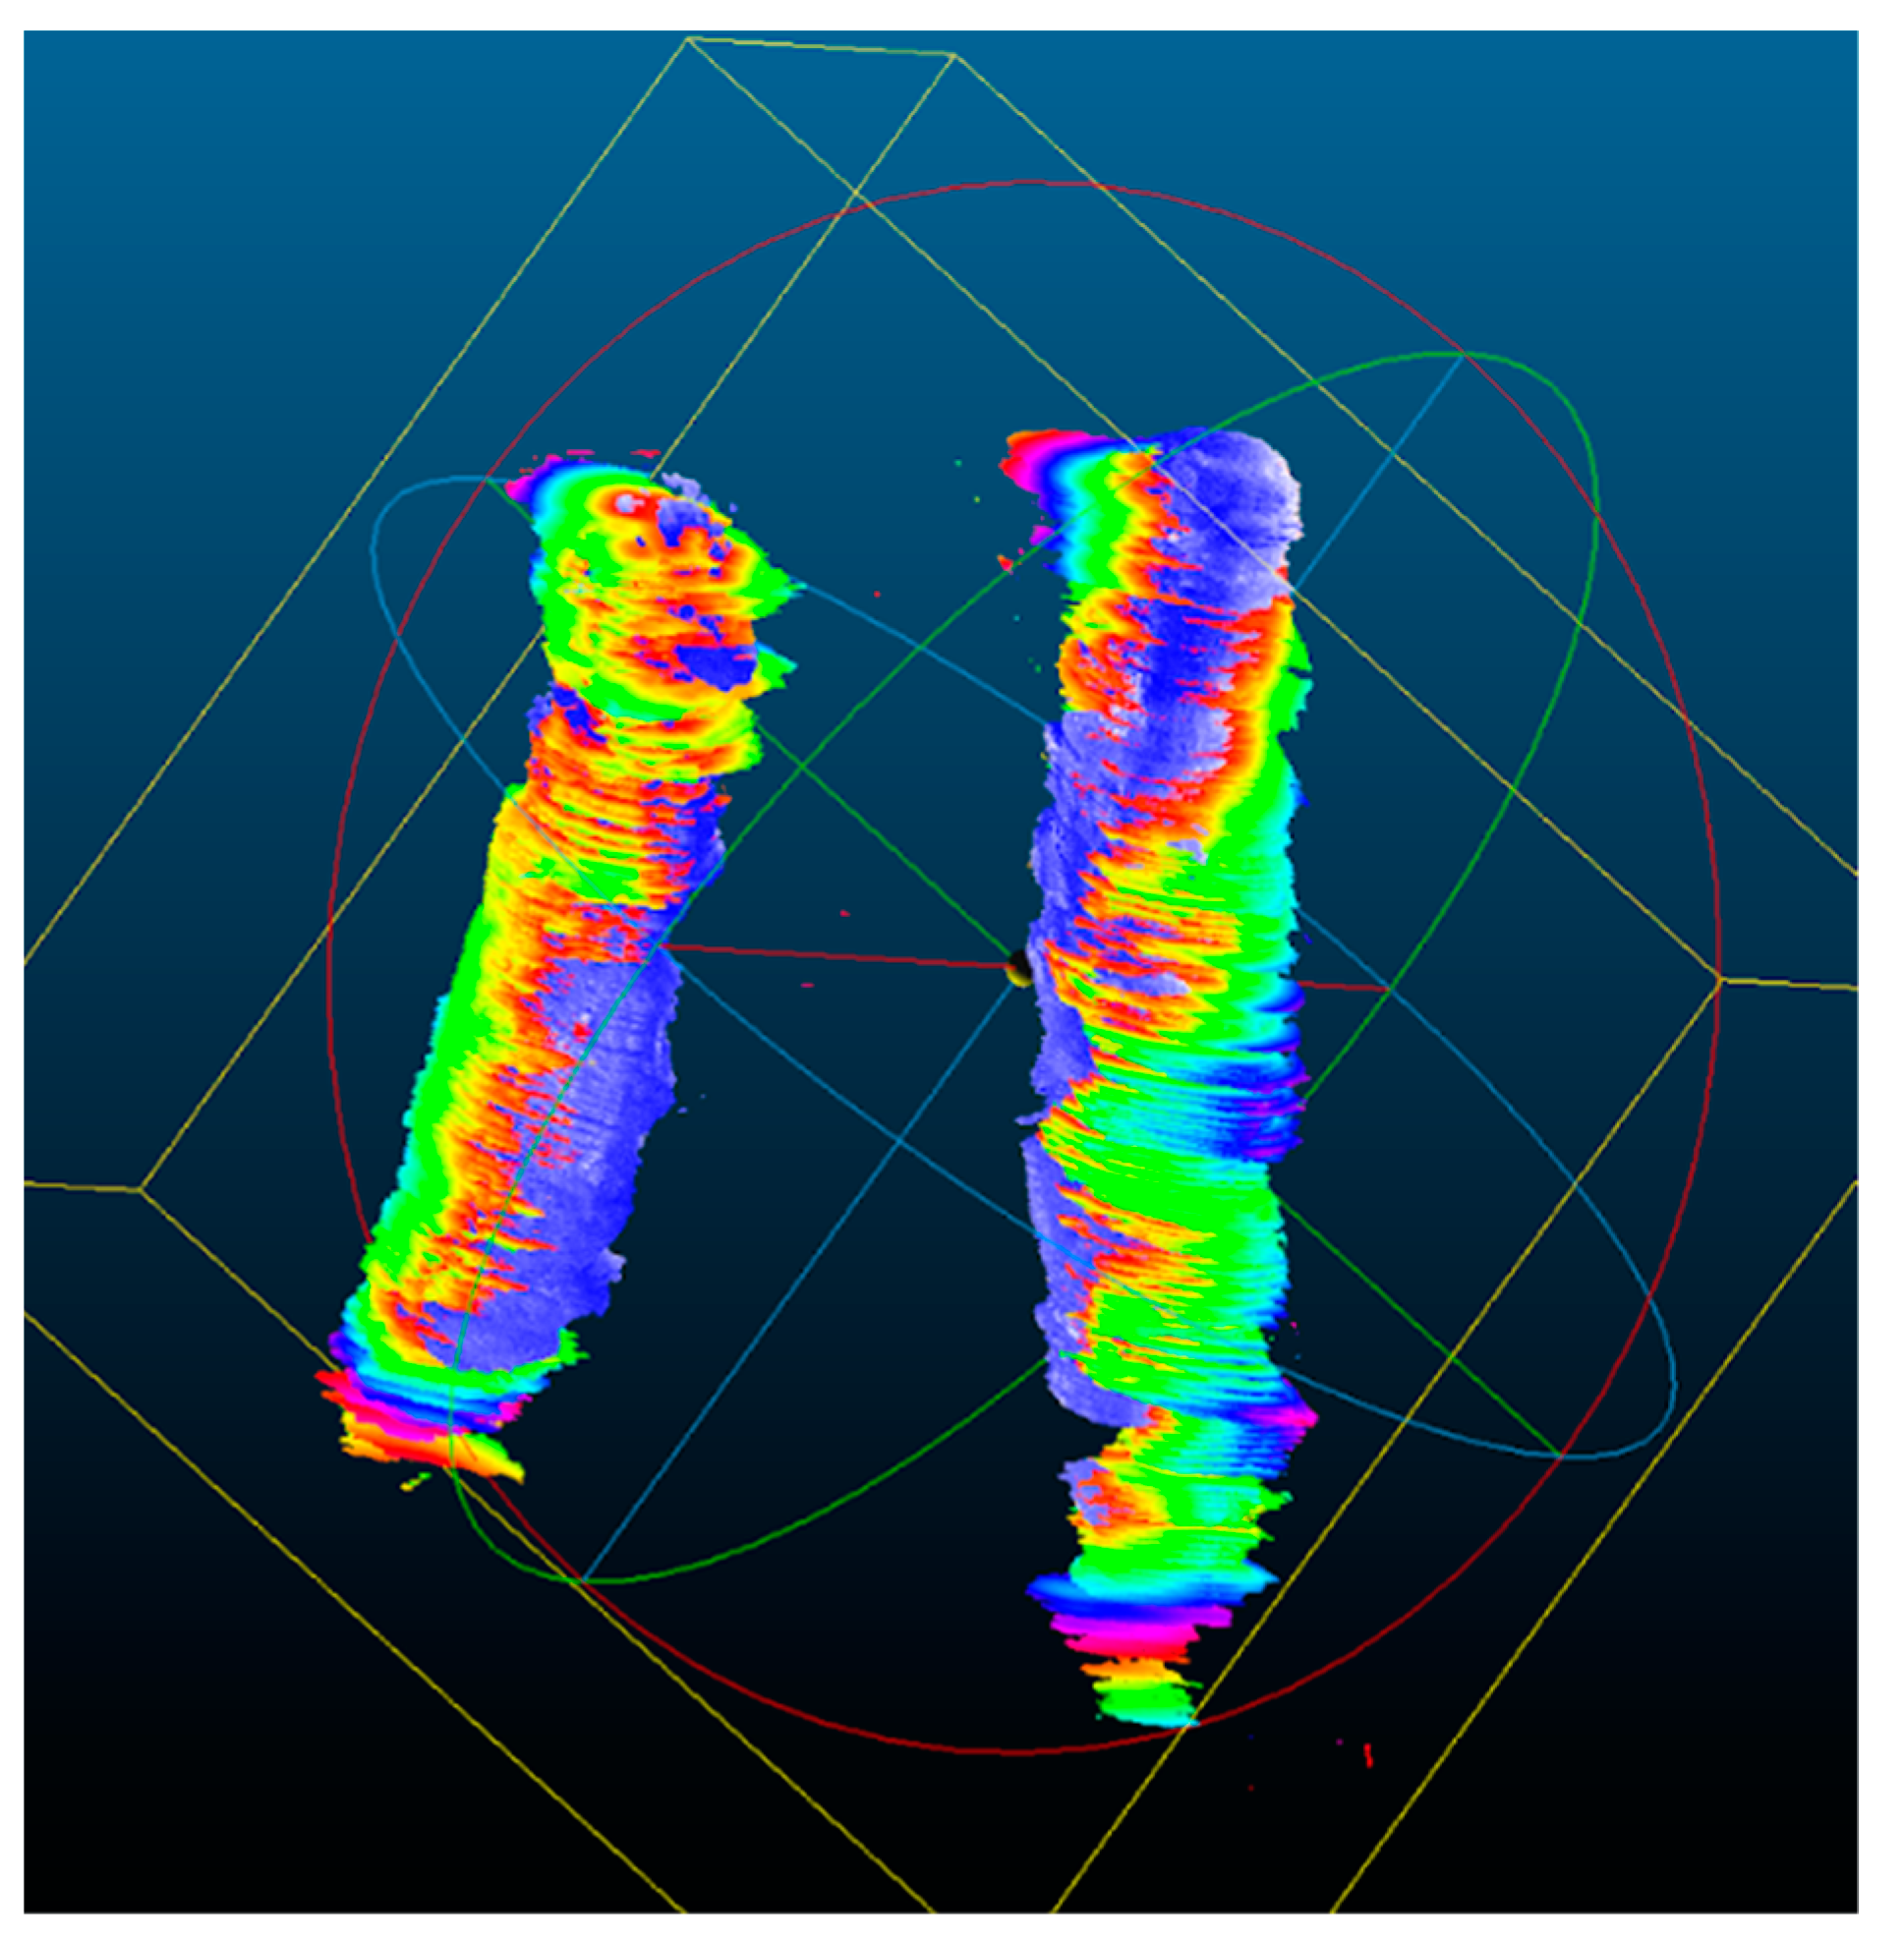

2.7. 3D Ultrasound Reconstructions of the Carotid Arteries

2.8. Qualitative Analysis of the 3D US Reconstructions

3.2. 3D US Reconstruction Compared with CT Angiography

3.3. Quantitative Analysis for the 3D US Reconstruction Based on Automated Mask Segmentation